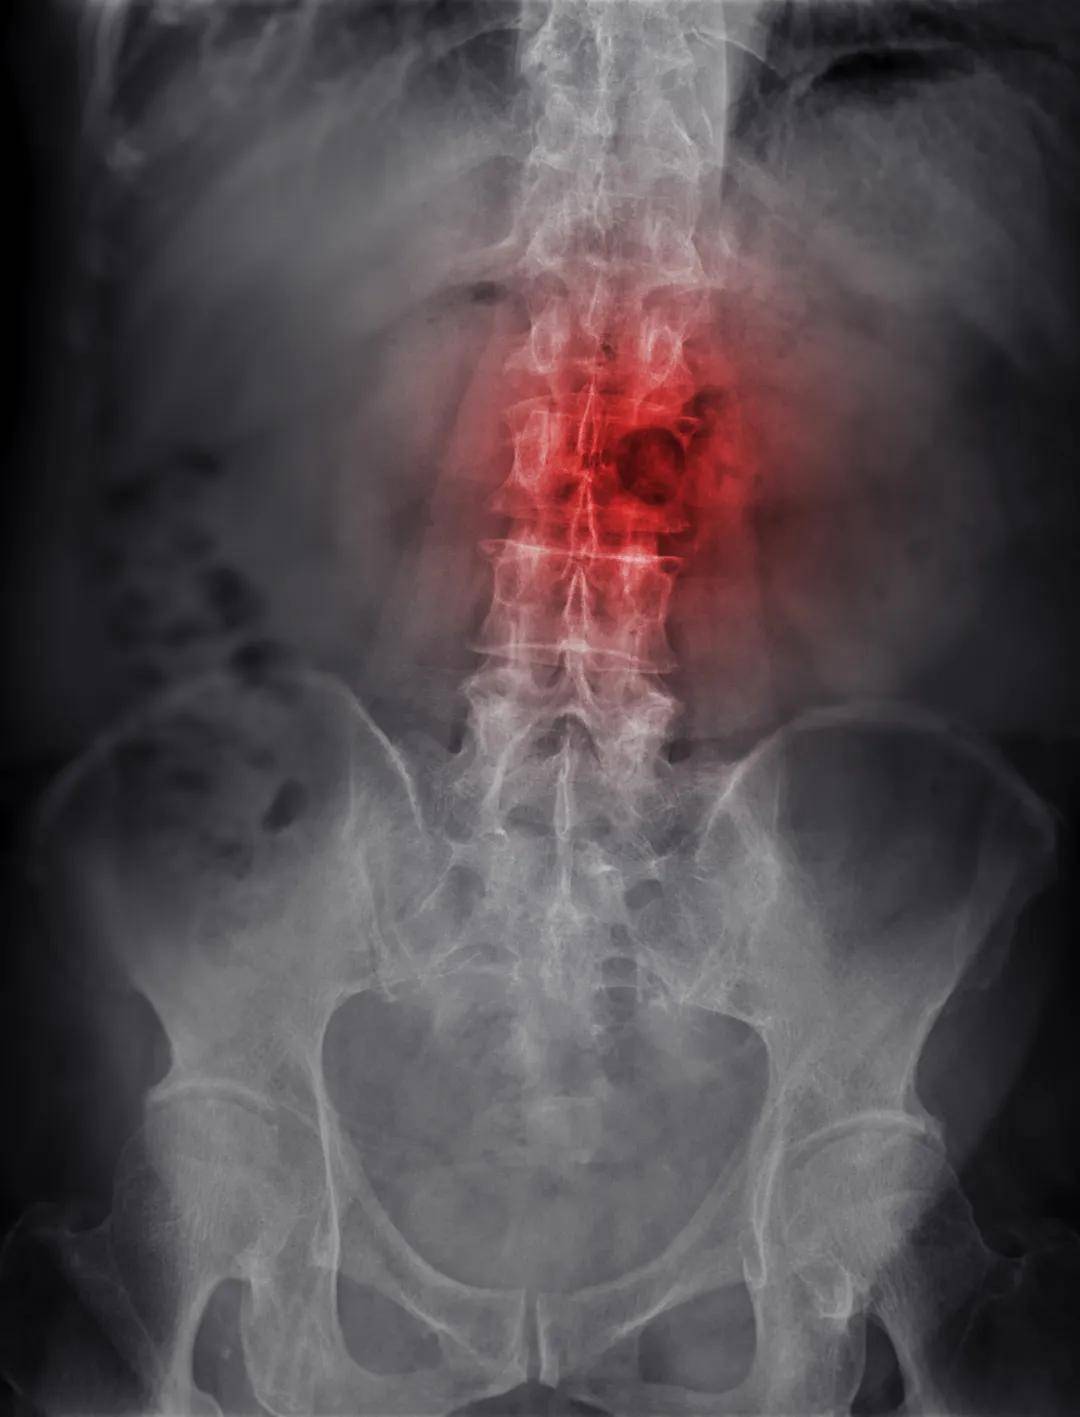

1. 固定部位骨痛,夜间加重

不同于运动后的酸痛,骨转移预警痛多固定在脊柱、肋骨、四肢等部位,呈持续性钝痛或刺痛,夜间平躺时痛感会明显加剧,服用普通止痛药效果不佳。中医认为这是“癌毒瘀阻经络,气血不通则痛”的表现。